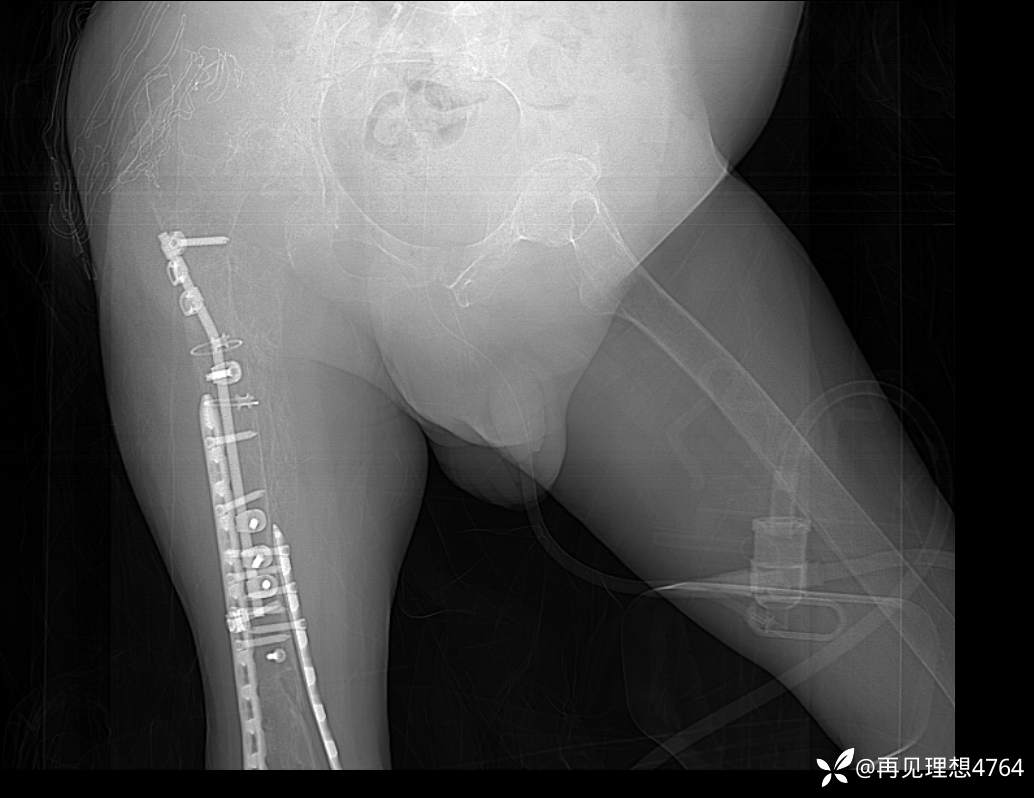

1、既往史:2年前因外伤致右下肢骨折于外院行“骨折切开复位内固定术”。1年前因压疮于外院行“左腹部取皮,骶尾部植皮术”。10个月前右股骨骨折,于外院行骨折内固定治疗,术后伤口感染不愈合,先后两次行“右侧臀部清创修复术”。6个月前因“右臀部感染”就诊于我院,于2025-3-27行“右股骨骨折术后感染切开清创引流术”,后使用VSD持续负压吸引。2个月前行右侧股骨骨折内定定物取出术。于2025-03-28输入400ml血浆及2U红细胞悬液;03-30输入400ml血浆及2U红细胞悬液;04-23输入200ml血浆及4U红细胞悬液;05-2输入400ml血浆及2U红细胞悬液;05-12输入400ml血浆及4U红细胞悬液。“2型糖尿病”病史10年,规律服用“二甲双胍缓释片”控制不佳;否认高血压病史;否认脑血管疾病史,无肝炎史、结核史、伤寒史,预防接种史不详。对“头孢类药物”过敏;否认食物过敏史。

初步诊断:1、右股骨骨髓炎(右髋部);2、截瘫;3、2型糖尿病;4、泌尿系感染;5、贫血;6、胸椎骨折术后;7、右股骨、胫骨骨折术后;8、冠心病(三支病变)。

下一步讨论准备术前准备,行右下肢截肢术。大家怎么分析?